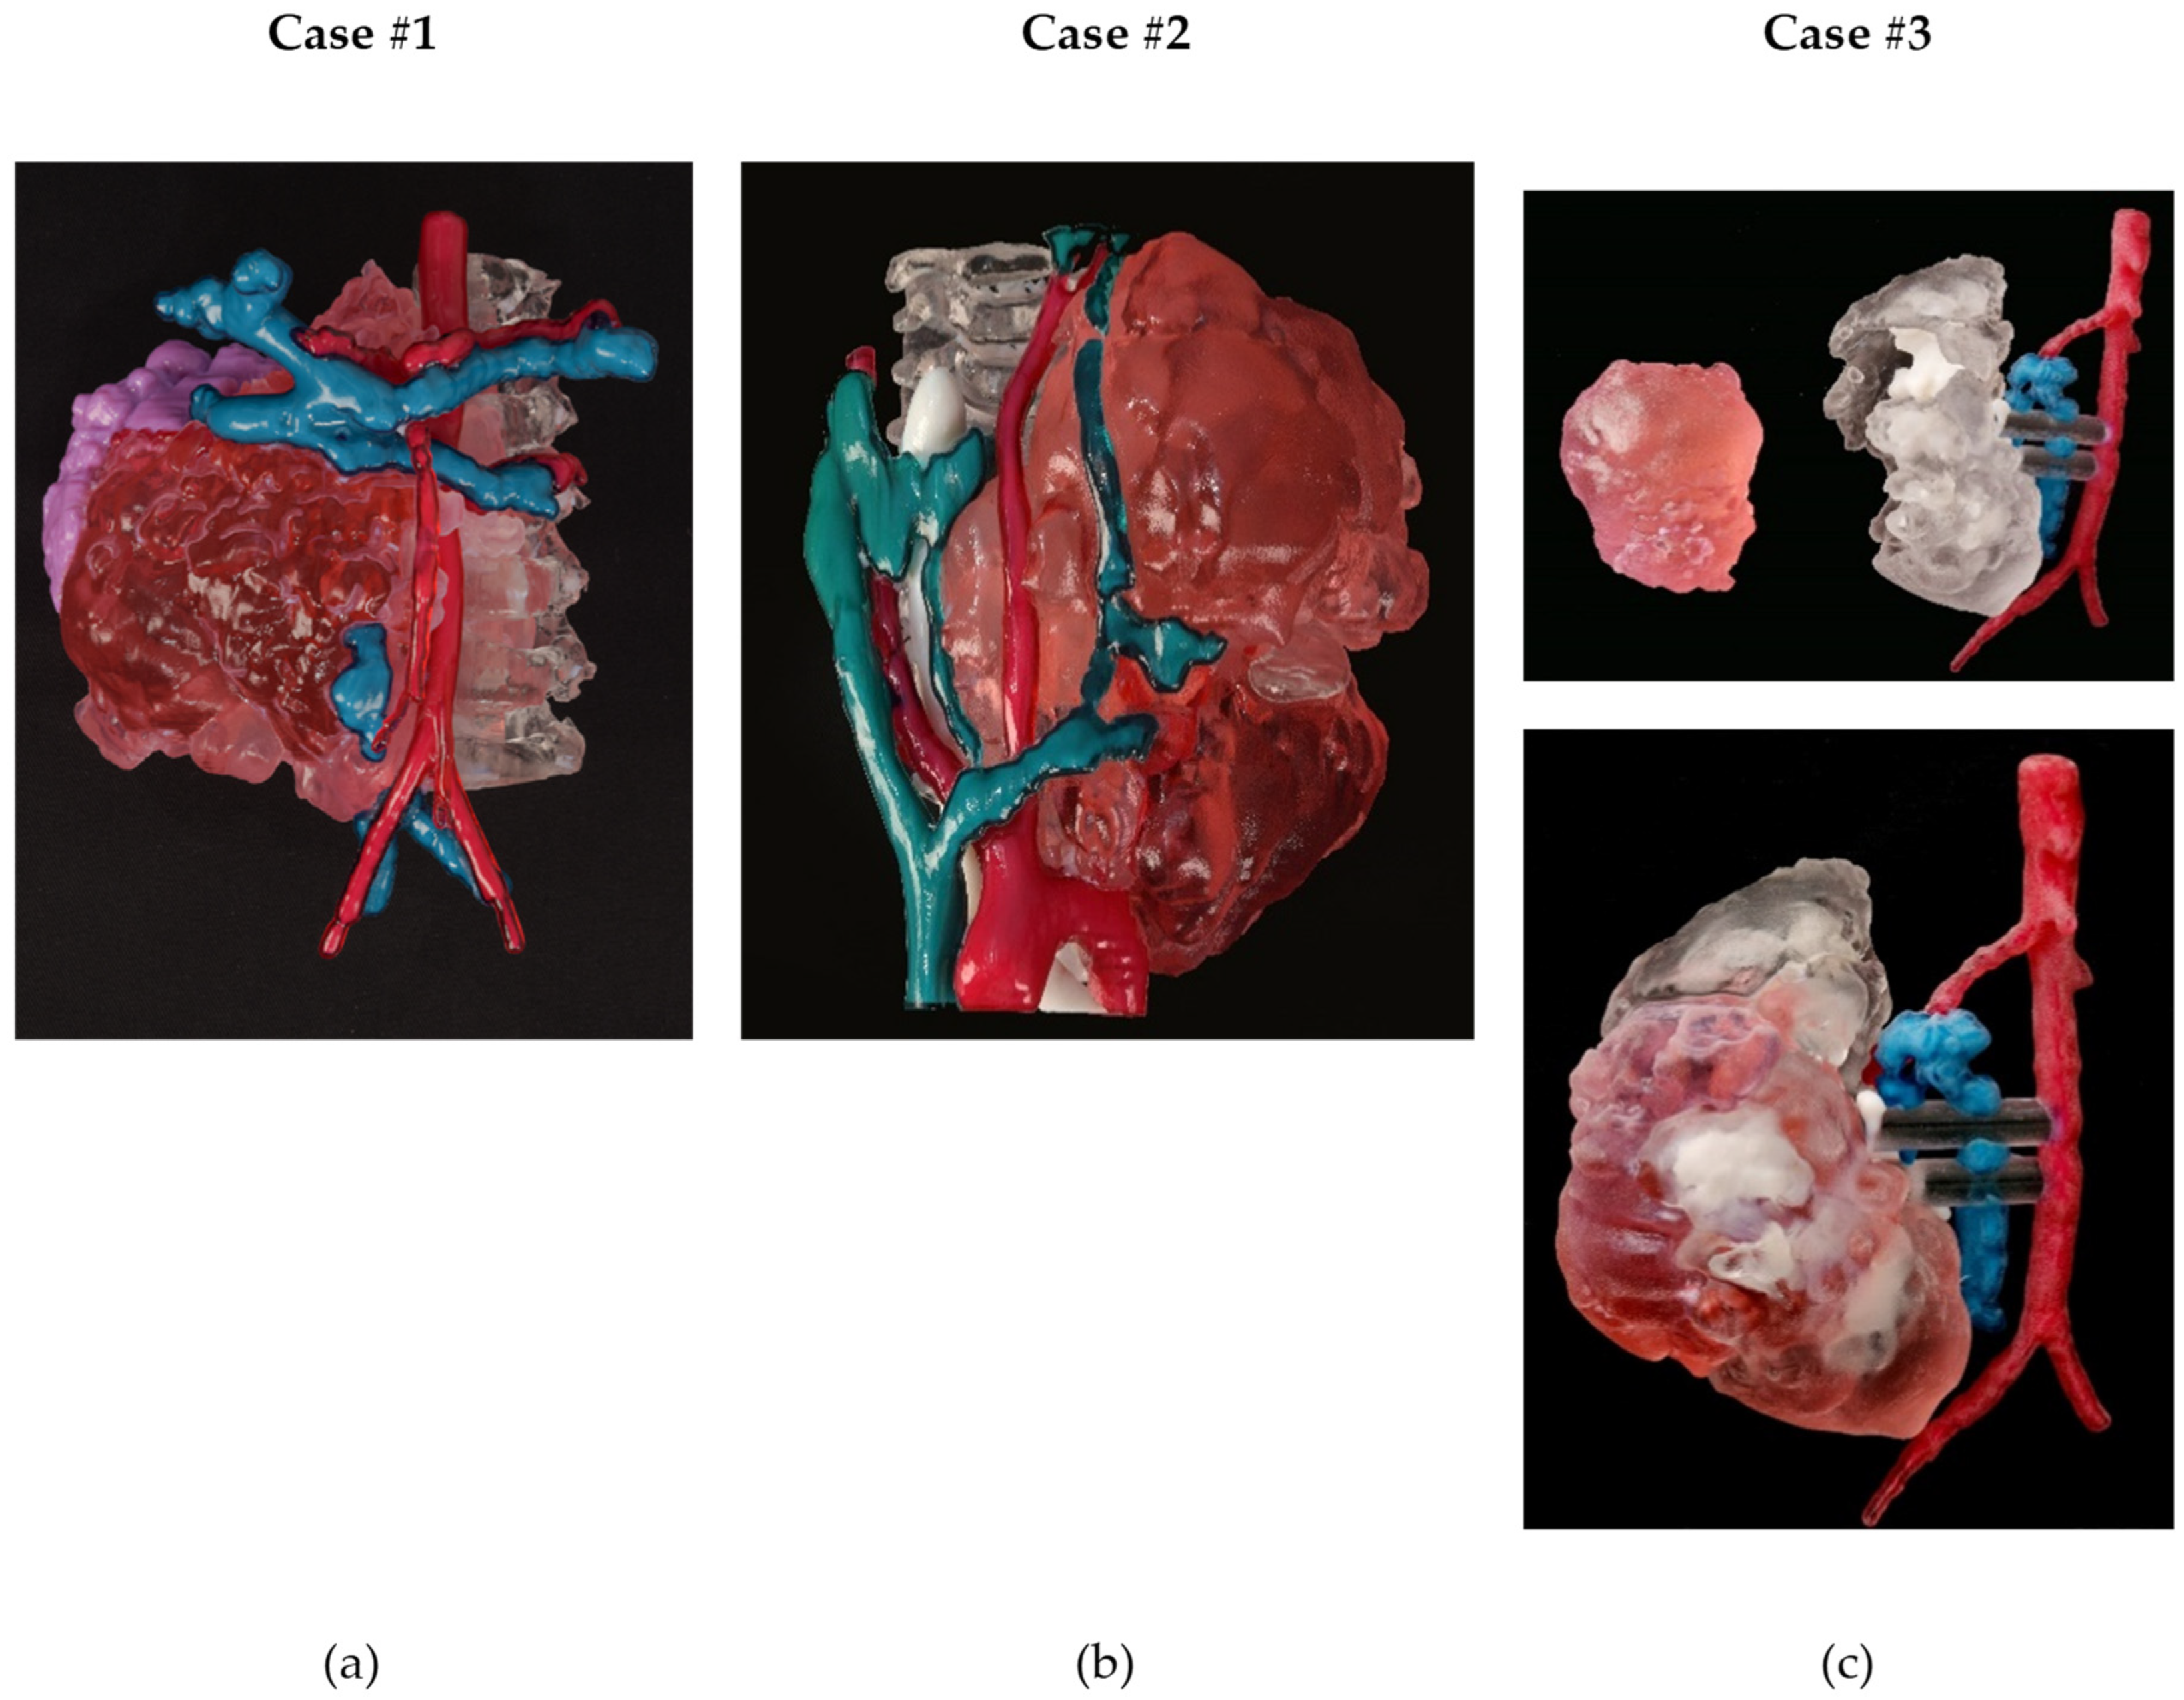

3.1.5. Three-Dimensional Printing

| Case | Technology | Printer | Printing Time | Cost | Model Materials | Support Material |

|---|---|---|---|---|---|---|

| 1 | Material Jetting | J5 MediJet© | 1 day 12 h 36 min | EUR 486,70 | VeroCyan™V for veins, VeroMagenta™V for arteries, Med610 for bone; tumor was printed with a combination of VeroMagenta™V + Elastico Clear with 60A shore hardness | SUP710™ (Water removable) |

| 2 | Material Jetting | J5 MediJet© | 24 h 21 min | EUR 435,51 | VeroCyan™V for veins, VeroMagenta™V for arteries, Med610 for bone, DraftWhite for airway; tumor was printed with a combination of VeroMagenta™V + Elastico Clear with 60A shore hardness | SUP710™ (Water removable) |

| 3 | Material Jetting | J5 MediJet© | 10 h 56 min | EUR 130,33 | VeroCyan™V for veins, VeroMagenta™V for arteries, Med610 for the kidney, DraftWhite for calyces; tumor was printed with a combination of VeroMagenta™V + Elastico Clear with 60A shore hardness | SUP710™ (Water removable) |